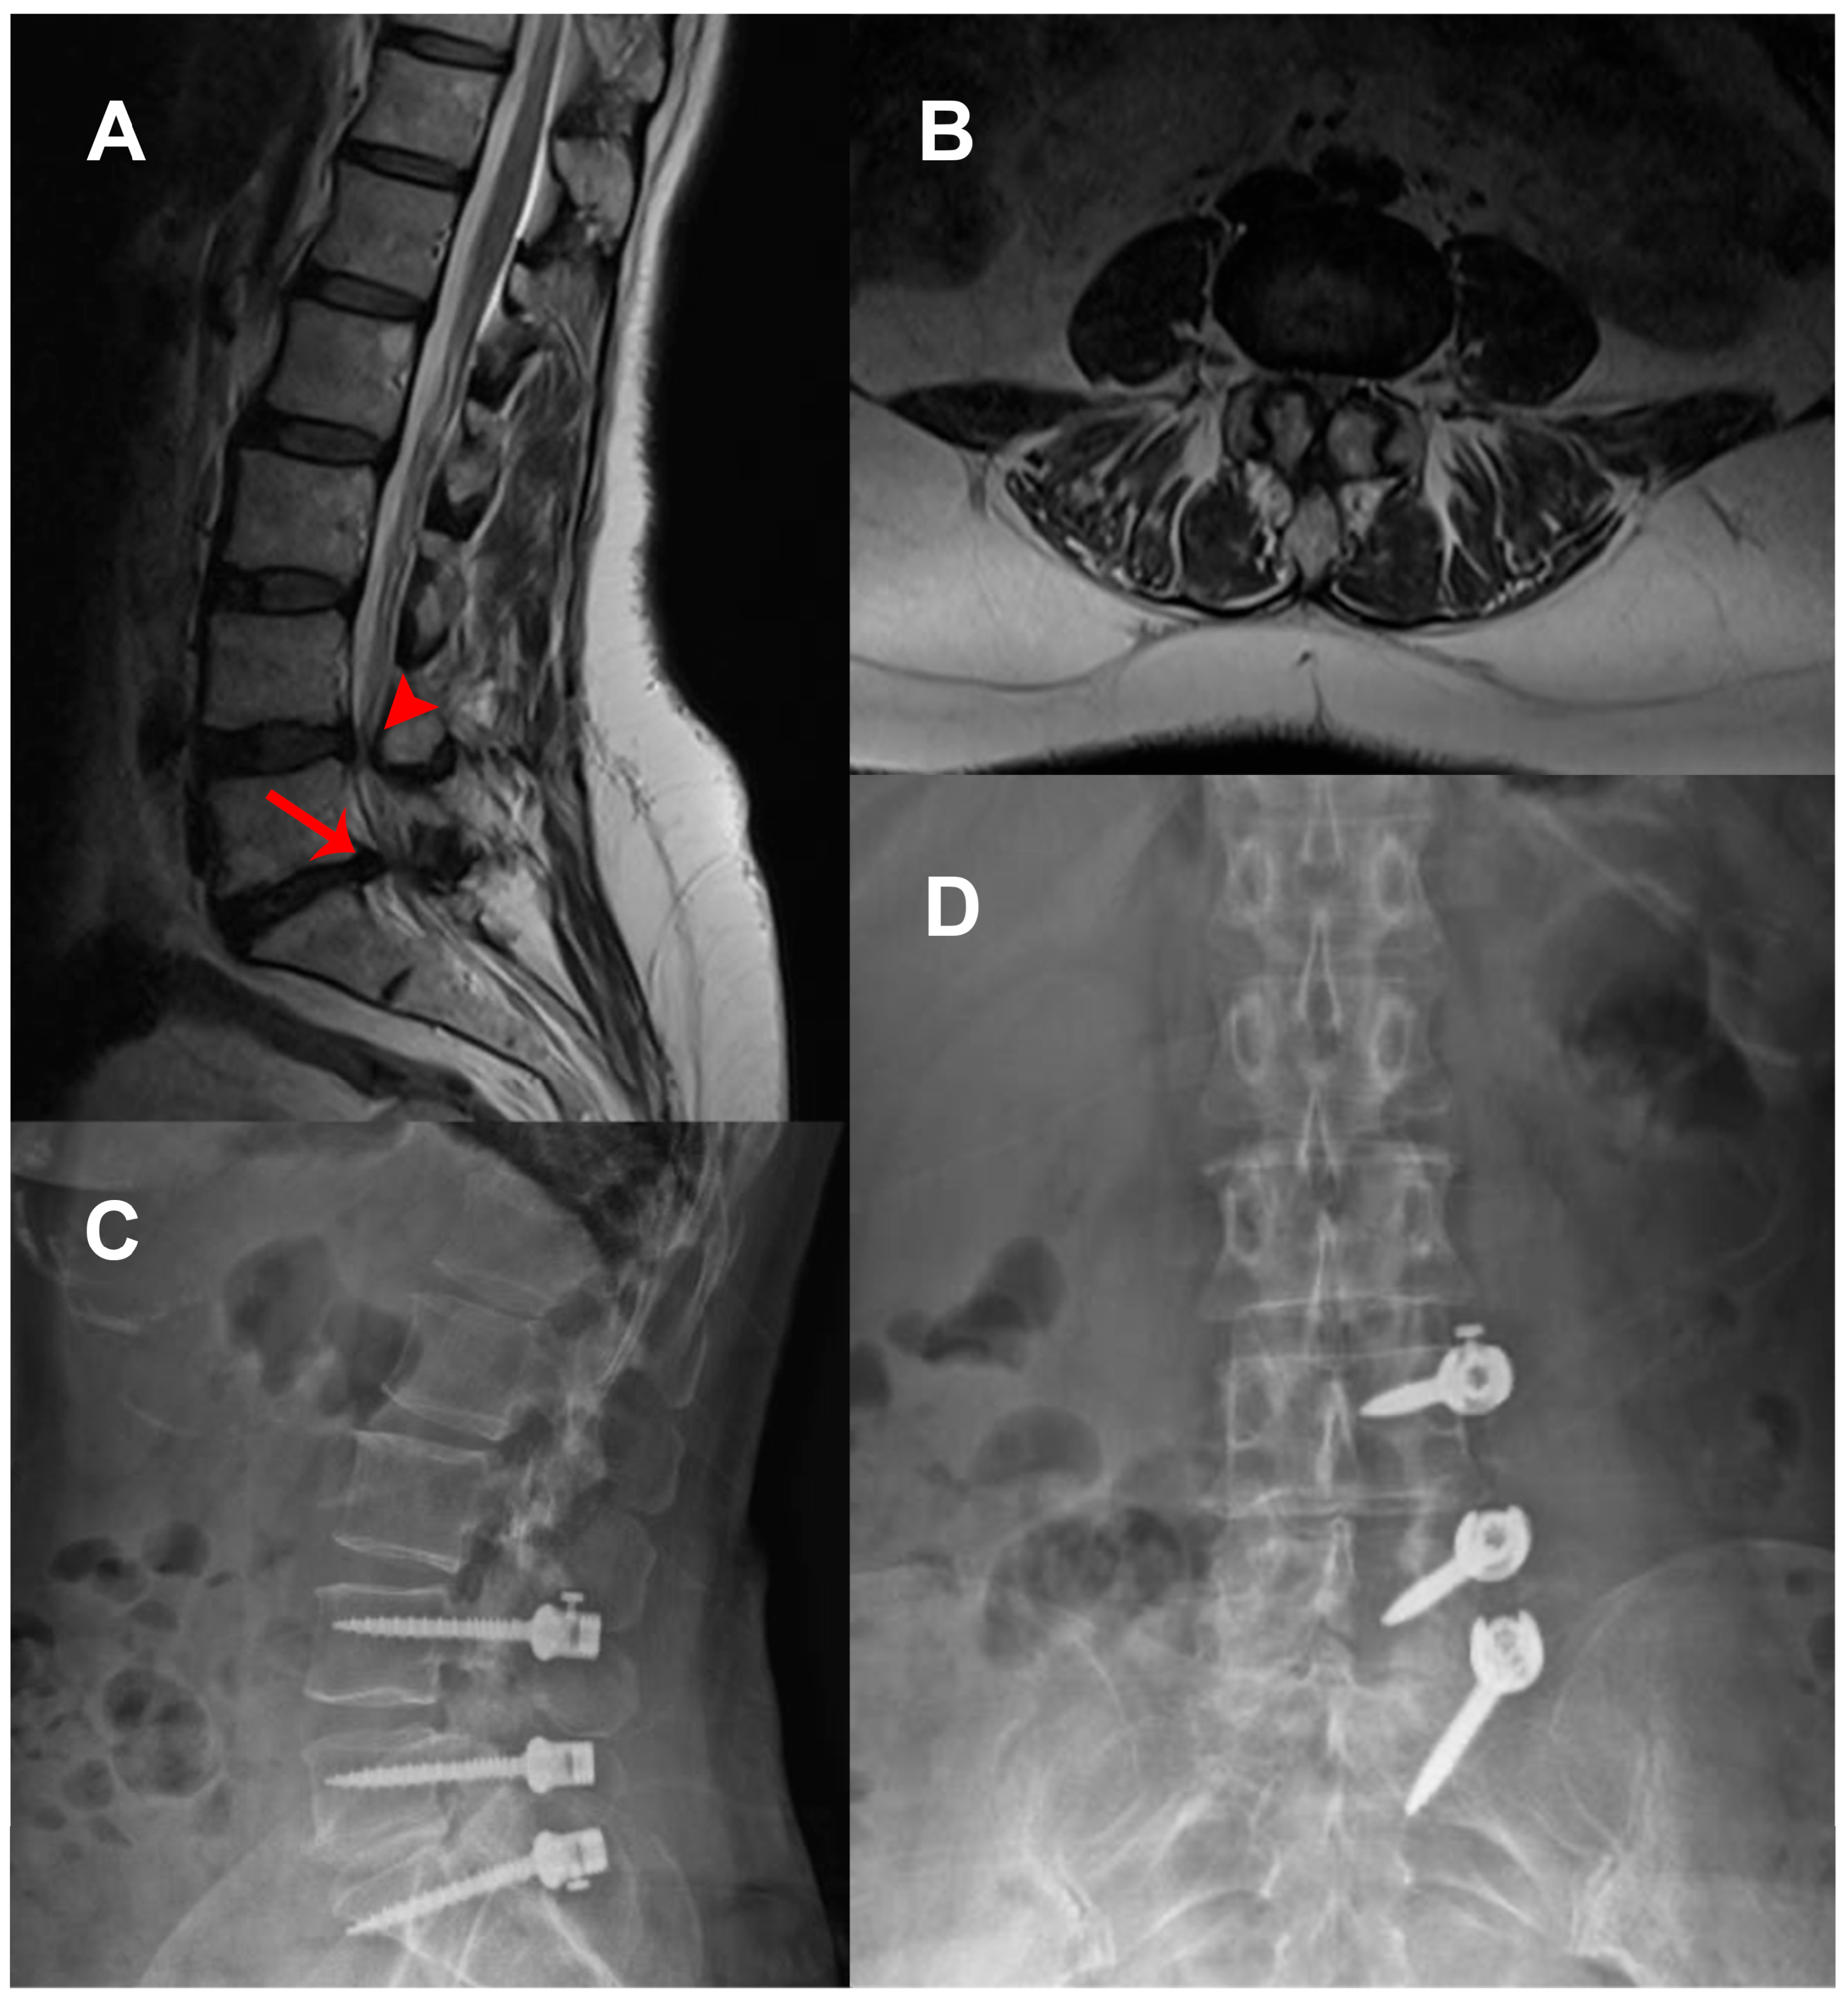

2.3. Surgical Technique